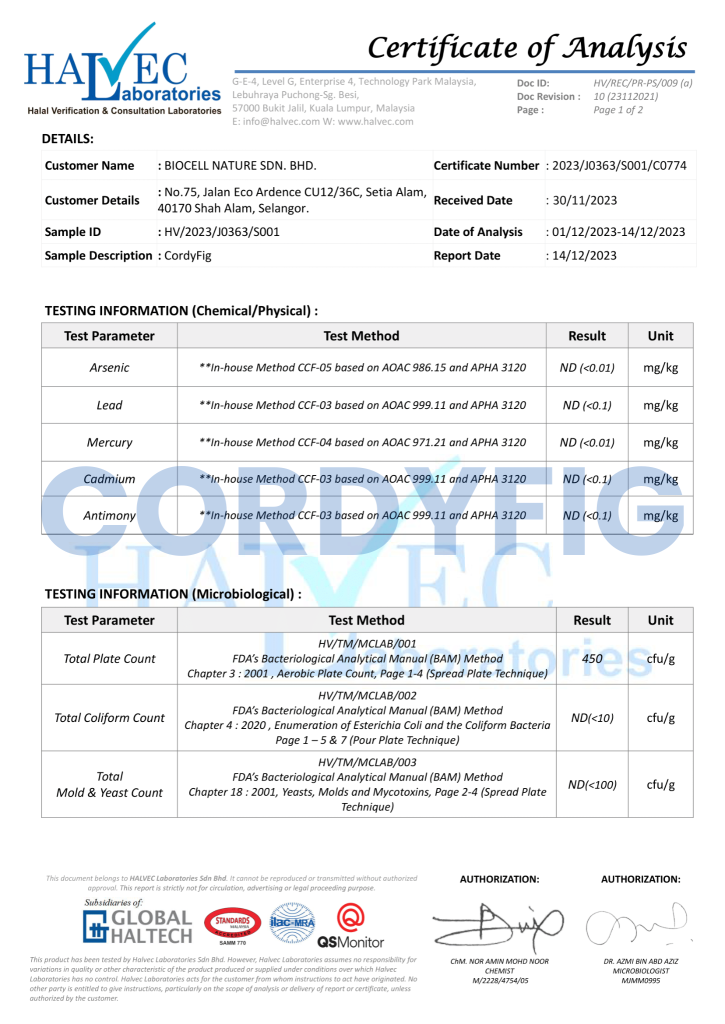

Jangan Risau ! Cordyfig Ada Kelulusan & Sijil Sah

Cordyfig Diperakui Oleh Pakar Dan Juga Terbukti Dengan Sijil Lulus Ujian Makmal Dan Pengesahan Halal JAKIM.

Gunakan Tanpa Was-Was. Tiada Unsur Yang Akan Merbahayakan Tubuh Badan Anda. Selamat Untuk Diamalkan!

Ada kesan sampingan yang berbahaya ke?

Tiada kesan sampingan sebab ianya adalah kategori makanan tambahan dan bukan ubat. Berasaskan 100% bahan semulajadi dan telah lulus ujian makmal